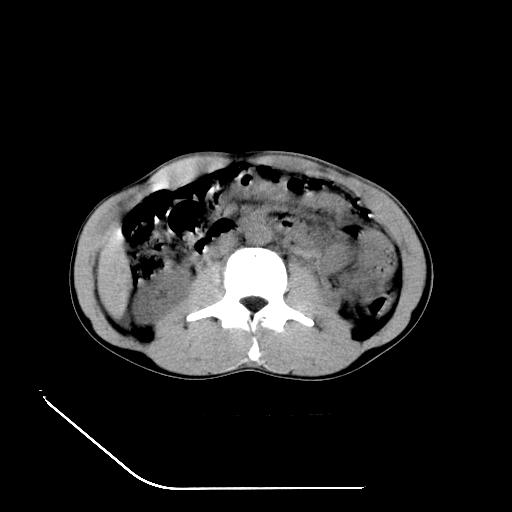

m-25y 高空堕落 12 月5号

12月7号病人尿量200ml/24h 急查双肾ct

左肾挫裂伤并肾周血肿;

肝肾间隙可见液区,建议手术探查;

左肾挫裂伤并肾周血肿

支持 : 左肾挫裂伤并肾周血肿

支持:1、左肾挫裂伤并肾周血肿;

2、少量腹水;

3、左肾旋转不良;

4、反射性肠淤张。

除了1:左肾挫裂伤并肾周血肿;

2:少量腹水

第二次ct检查后:临床医生腹水穿刺后考虑肠系膜动脉破裂,后实行剖腹探查:于空肠距离十二指肠90cm处发现肠管破裂,破裂口较小;修补后关腹。